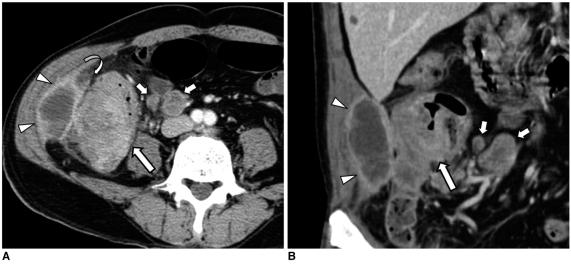

结肠癌相关结肠并发症的 CT 表现

CT findings of colonic complications associated with colon cancer.

A broad spectrum of colonic complications can occur in patients with colon cancer. Clinically, some of these complications can obscure the presence of underlying malignancies in the colon and these complications may require emergency surgical management. The complications of the colon that can be associated with colon cancer include obstruction, perforation, abscess formation, acute appendicitis, ischemic colitis and intussusception. Although the majority of these complications only rarely occur, familiarity with the various manifestations of colon cancer complications will facilitate making an accurate diagnosis and administering prompt management in these situations. The purpose of this pictorial essay is to review the CT appearance of the colonic complications associated with colon cancer.

结直肠癌患者可能会出现广泛的结肠并发症。临床上,这些并发症中的一些可能会掩盖结肠中潜在的恶性肿瘤,这些并发症可能需要紧急手术治疗。可能与结直肠癌相关的结肠并发症包括梗阻、穿孔、脓肿形成、急性阑尾炎、缺血性结肠炎和肠套叠。虽然这些并发症大多数很少见,但熟悉结直肠癌并发症的各种表现形式将有助于在这些情况下做出准确的诊断并进行及时的治疗。本文旨在通过 CT 影像回顾结直肠癌相关结肠并发症的表现。